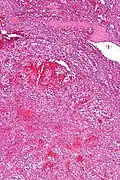

Littoral cell angiomas show in CT scans. They are diagnosed by pathologists by taking a sample of the tumour via Fine Needle Aspiration or Core Needle Aspiration or from a splenectomy. Histologically, they have anastoming small vascular channels and cystic spaces with papillary projections.[2]

Very low mag. -